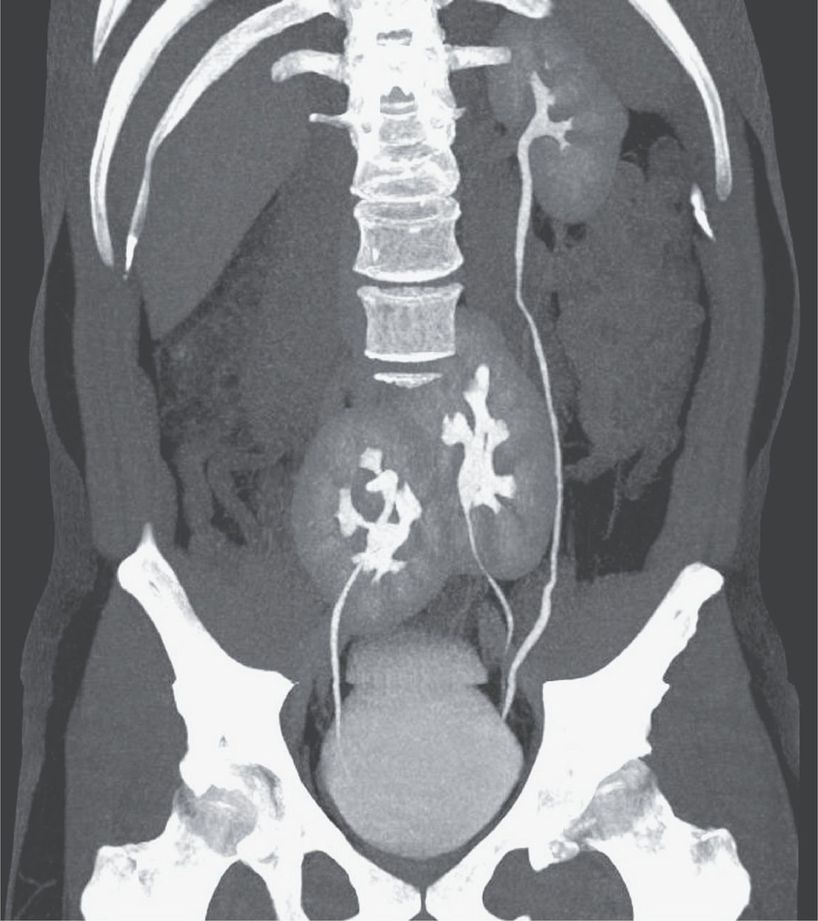

A 38-year-old man presented to the outpatient clinic with severe low back pain. As part of the evaluation, computed tomography (CT) was performed. The scan incidentally showed the presence of three kidneys: a normal-appearing left kidney and two fused kidneys in the pelvis. The ureter from the left pelvic kidney joined the ureter from the other left kidney just above its entrance into the bladder. The ureter from the right pelvic kidney entered the bladder on the right side. The CT scan also showed a herniated disk between L4 and L5. Renal function was normal, with a creatinine level of 0.9 mg per deciliter (80 μmol per liter) (normal range, 0.6 to 1.0 mg per deciliter [53 to 88 μmol per liter]). This uncommon congenital abnormality was thought to be the consequence of aberrant processes during embryogenesis. The duplicate left kidney may have resulted from a premature division of the left ureteral bud. In addition, the right and lower left developing kidneys fused and did not ascend during development. Affected persons are commonly asymptomatic, and as in this case, the condition may not become known until imaging is performed for another reason. The patient’s back pain was attributed to the lumbar disk herniation, and he was treated with an oral analgesic agent.